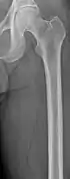

Multiple myeloma in the upper arm

Femur with multiple myeloma lesions

Same femur before myeloma lesions for comparison